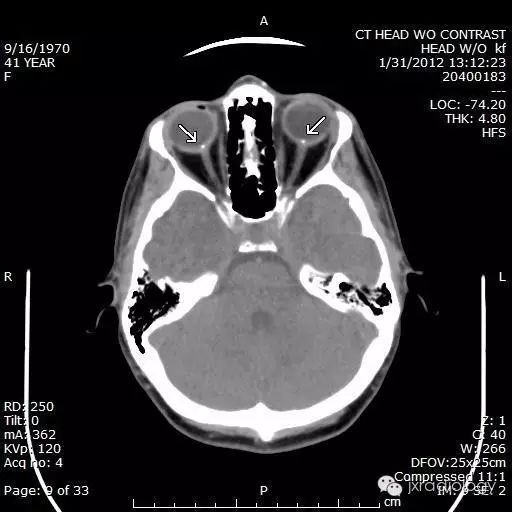

视乳头玻璃膜疣(Optic disc drusen,ODD)也称为透明小体或玻璃膜疣,是相对常见的病变。它们通常在CT或异常眼底镜检查的随访中偶然发现。

CT上的征象反映出玻璃膜疣含钙增多。

病例图片:

CT:虽然在儿童时期就能被识别出来,但它们很小,而且没有矿化。因此,在儿科病人中很少发现,尽管在薄层扫描中,密度和肿胀的区域可能很明显。

2.5视盘玻璃膜疣 视盘玻璃膜疣(optic disc drusen,ODD)是一种与视网膜玻璃膜疣名称相同而病理改变及发病机制迥异的疾病,其可分为原发性和继发性两种,后者继发于炎症和外伤。在此所述为与先天有关的原发性视盘玻璃膜疣。其发病机制有研究认为可能是基因突变引起;另有研究认为是因视神经纤维轴浆崩解、钙化或先天性的血管异常造成的血浆蛋白传输障碍郁积在视盘引起。电子显微镜下见玻璃膜疣多位于视盘筛板前区、视盘内有大小不一、呈环板状排列的无细胞结构的嗜碱性小体[2]。根据玻璃膜疣病变位置的深浅有可分为埋藏性玻璃膜疣和表面性玻璃膜疣。表面性玻璃膜疣眼底检查可见视盘结节状胶样隆起,并可融合为不规则的较大团块向玻璃体内突出如桑葚状,较易诊断。埋藏性ODD的眼底影像学表现显示视乳头轻度隆起,边界欠清晰,有时显示假性视乳头水肿。因疣体压迫、损伤视乳头上或周围毛细血管,可引起视盘或其周围视网膜出血。自发荧光表现为视盘自发荧光。FFA对诊断埋藏性玻璃膜疣具有极其重要的价值,造影早期视盘局部荧光素明显增强,造影后期玻璃膜疣处荧光素染色明显,但无荧光素渗漏。OCT检查可见患眼视盘视网膜神经纤维层(RNFL)高度隆起,其下方可见团块状高反射信号。B超是诊断ODD最有效的方法,因疣内存在钙质,检测结果会显示有强回声光团存在于视盘强方,其周边显示呈暗区,降低增益,光团不消失。有研究[18]发现对埋藏性视盘玻璃膜疣使用B超联合OCT检查,是非常可靠的诊断方法,两者联合应用,可有效提高检出率。有学者[19]认为,将玻璃膜与视网膜色素上皮层之间的drusen定义为玻璃膜疣,而将发生在视盘的drusen定义为视盘玻璃疣,这样可以更加明确drusen的概念。3 总结